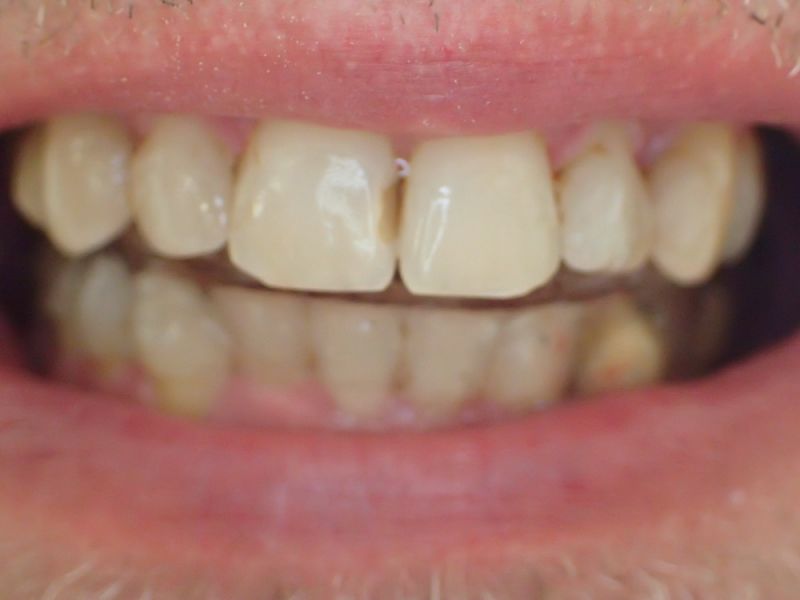

2. Herstellung und Eingliederung eines adjustierten Aufbissbshelfs

Erkennbar ist die massive Abweichung der habituellen Bisslage von der neuromuskulär zentrierten Bisslage.